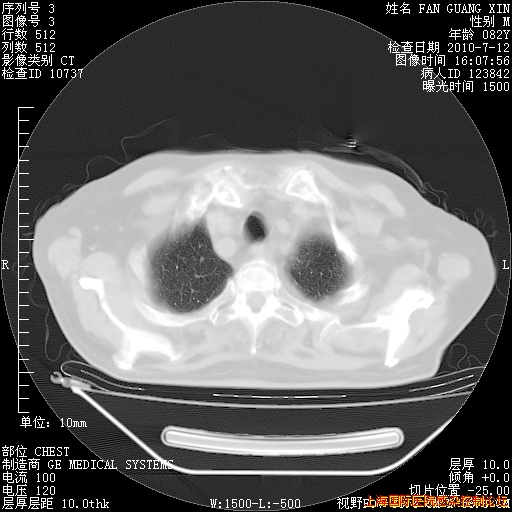

今天复查CT

今天CT

整整相隔30天的肺部CT好像有所好转啊。甲强龙减量第3天,需要观察体温。